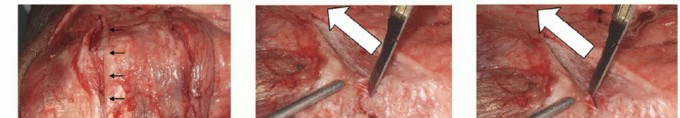

- TECH FIG 3 • A. The triceps is split through its central tendon in line with the fibers. The tendinous portion is dissected from the olecranon to gain access to the ulna. B,C. To dissect the Sharpey fibers off the ulna, the surgeon uses the scalpel parallel to the ulna surface and maintains the release directly adjacent to the bone. (continued)

Preserving the integrity of the triceps insertion makes component insertion more difficult. An alternative approach for managing the triceps is to reflect it from the tip of the olecranon from medial to lateral, thereby improving exposure (TECH FIG 3).

Define the medial triceps border and dissect the ulnar nerve free from its connections while protecting it in a vessel loop. The nerve is transposed into a subcutaneous pocket.

The medial triceps is dissected to its ulnar attachment. Release the triceps from the medial condylar fragments, and transect the medial collateral ligament. Free the medial fragments from soft

tissue attachments, and remove the medial fragments between the triceps and a gently anteriorly retracted ulnar nerve.

TECH FIG 3 • (continued) D. Comminuted distal humeral fracture in an osteoporotic elderly woman, with CT imaging confirming significant articular comminution. This is the view through the triceps split.